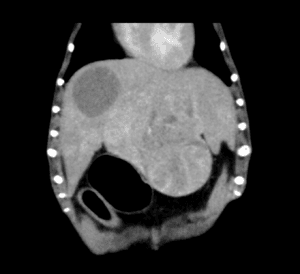

犬の副腎腫瘍は、大きく臨床症状を示す「機能性腫瘍」と、症状を示さず画像検査で偶発的に見つかる「副腎偶発腫」に分類されます。副腎は外側の皮質からコルチゾールなどのステロイドホルモンを、内側の髄質からカテコラミンと呼ばれるホ […]